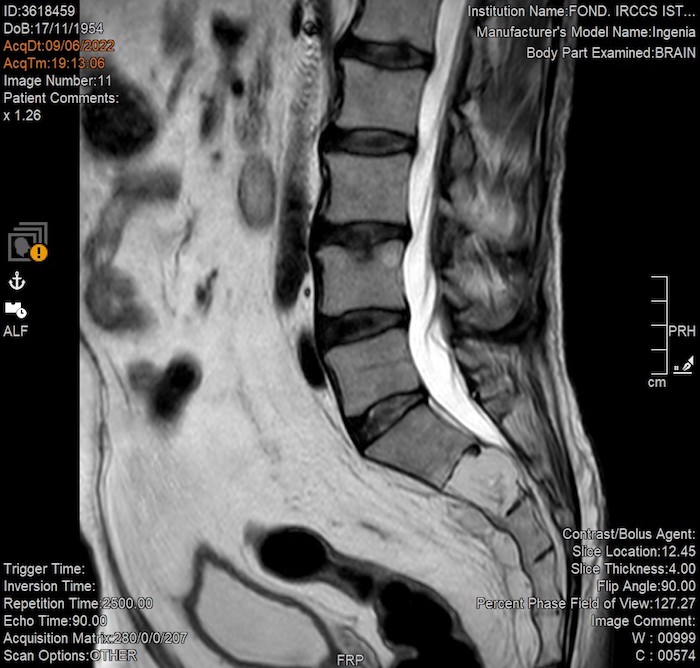

MZ: Esiste probabilmente un punto di rottura tra la necessità del referto e lo stupore della forma. In risonanza, i parametri T1, T2 o le sequenze pesate in diffusione cambiano radicalmente il contrasto e l’aspetto dei tessuti. Un artista può utilizzare questi “strumenti di contrasto” come se fossero filtri pittorici (o qualcosa del genere) e cosa può trovare o individuare nelle immagini registrate durante una risonanza magnetica?

DS: Certamente le scelte tecniche (immagini pesate in T1 o T2 o immagini in tecnica di diffusione) rispondono in momenti diversi dello stesso esame alla richiesta di risoluzione spaziale e risoluzione di contrasto. “Filtri pittorici” finalizzati direi. Detto questo direi che esiste un continuum senza soluzione fra estetica e finalità clinica. Anche in questo senso la medicina è un’arte, l’arte della cura, la cui via l’artista (in questo caso il medico) va cercando nelle immagini che con il tecnico e la macchina produce.

MZ: Il ritmo della RM potrebbe ricondurre in qualche modo a qualcosa che è simile alla sintesi granulare o il glitch. Hai mai trovato una corrispondenza visiva tra la “grana” dell’immagine prodotta e la frequenza acustica della sequenza (per esempio il passaggio tra un’eco di spin e una sequenza ultraveloce)?

DS: Esiste una precisa correlazione fra la tipologia di suono e la tipologia (sequenza, in gergo tecnico) di immagine. In linea di massima, in una data apparecchiatura, più veloce è la sequenza e maggiore sarà il “rumore” (in senso ottico) dell’immagine. Quindi risponderei dicendo che la granulosità è determinata dalla necessità di ottenere le immagini in un dato lasso di tempo (quante similitudini con la fotografia, sto pensando).